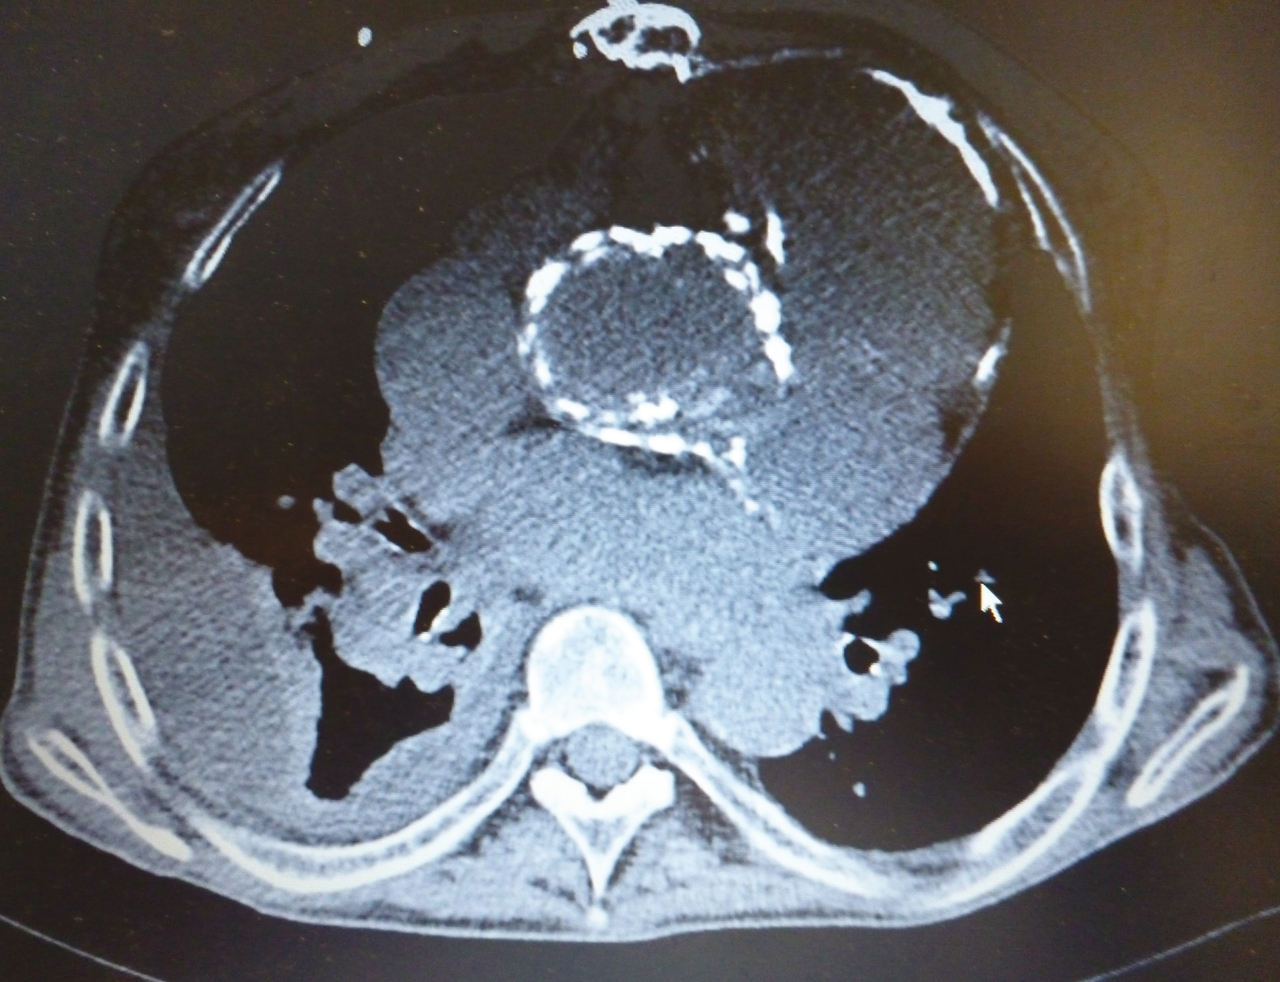

Il s'agit d'une prothèse valvulaire, mise en place suite à une intervention de Bentall.

Cette photo provient de la collection du Pr Olivier Fain (Hôpital Saint-Antoine, Paris).